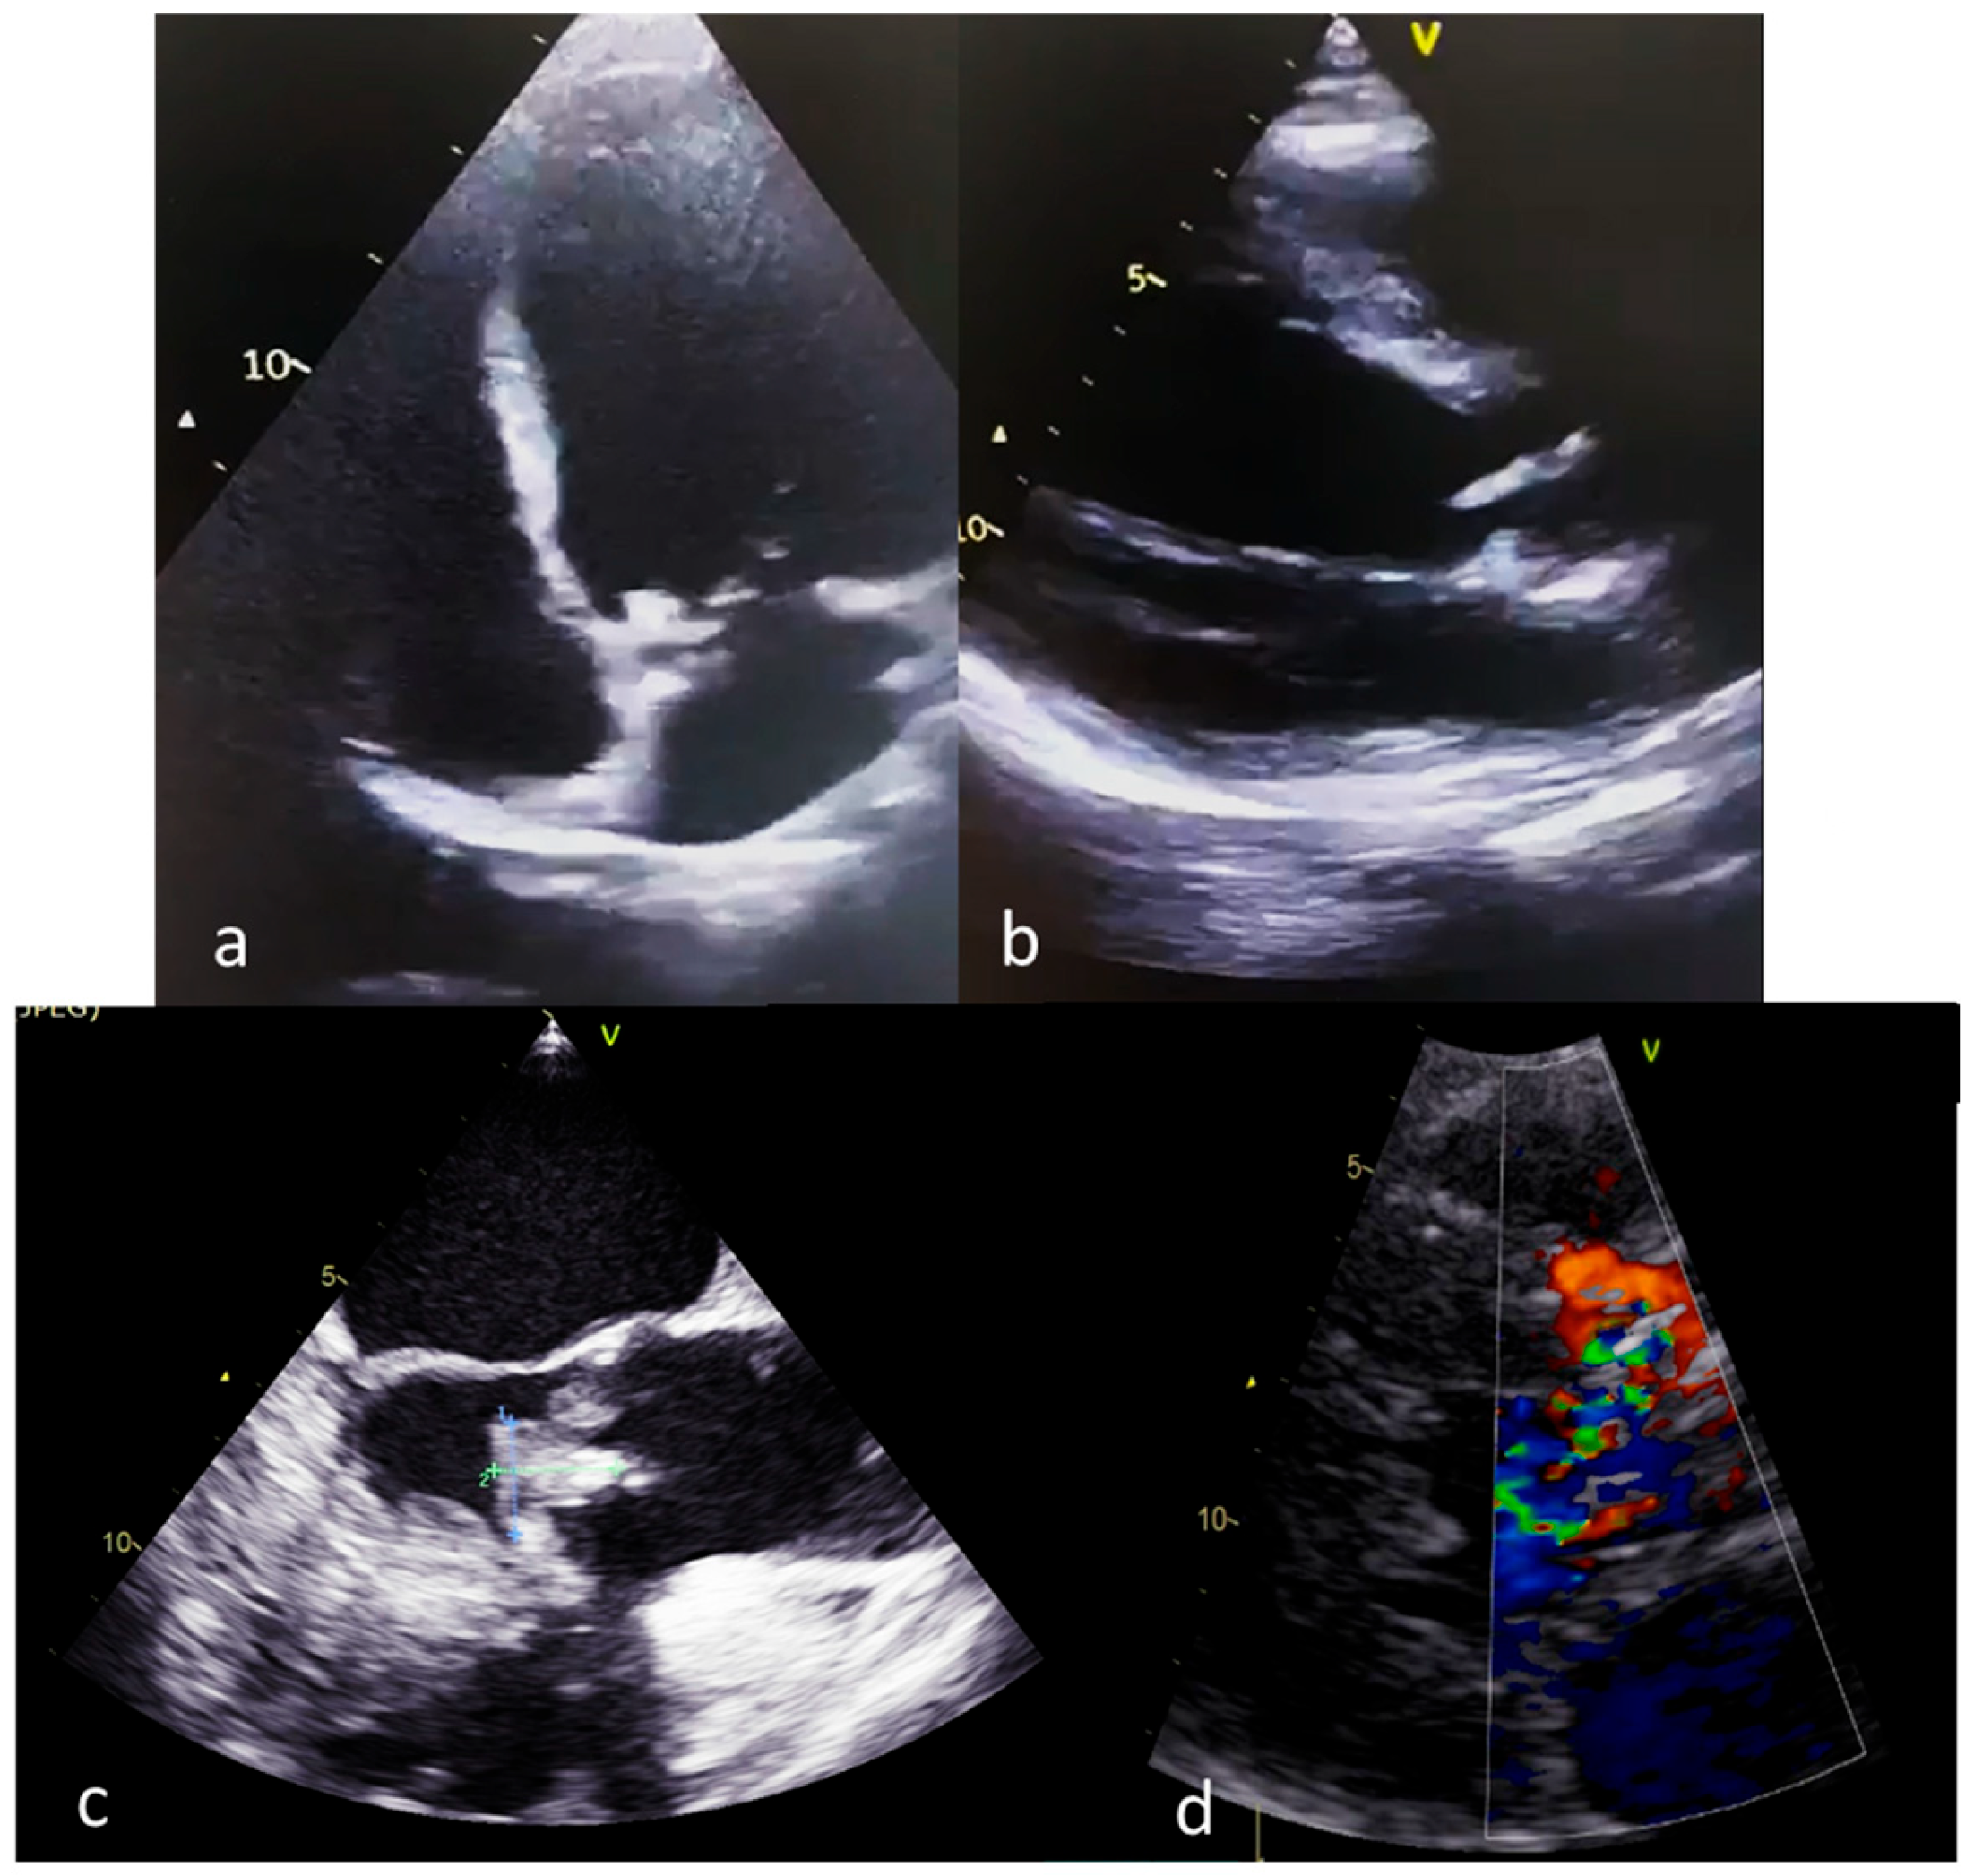

- Multimodal Imaging Assessment